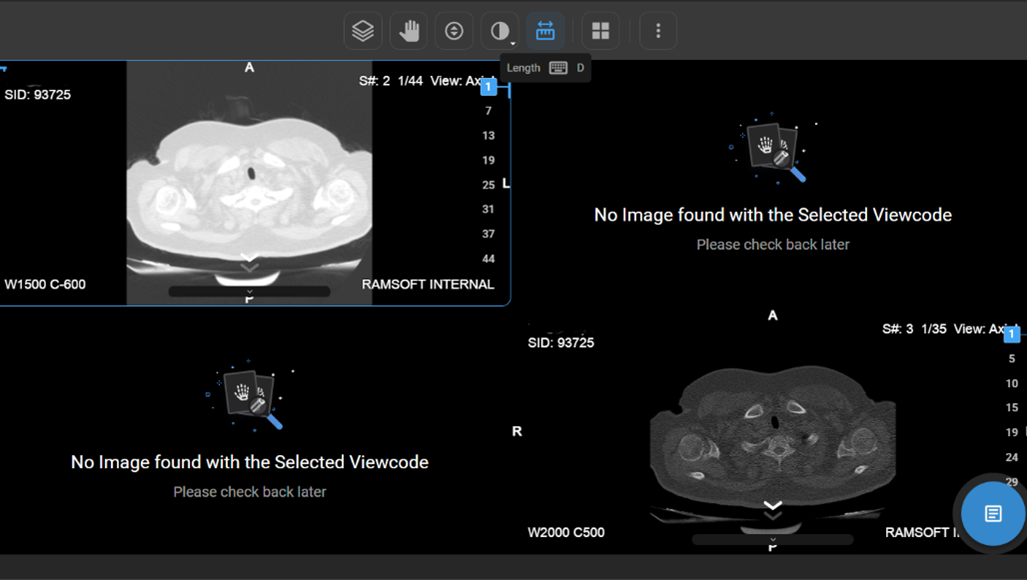

How Do I View Multiple Images or Series in Different Layouts?

• If there are multiple images or a series of images, you can customise the display layout to enhance your viewing experience.

• Locate and click on the Change Layout icon in the image viewer toolbar at the top of the screen.

vai

• Select the desired layout format to switch between a single-frame view and a multi-frame display for comparing multiple images simultaneously.

How Do I Change the Viewport Layout?

1. Open Layout Selector from the toolbar.

a. A 3×3 grid appears, with the current layout highlighted.

1. Adjust Viewports:

a. Drag to increase/decrease viewports (up to 8×8 grid per monitor).